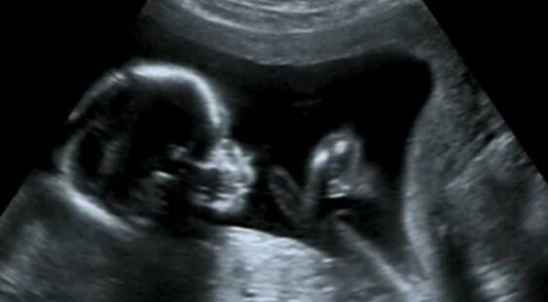

随着医疗技术的不断发展,B超系统作为一项重要的医学影像技术,已经在临床诊断中扮演着不可或缺的角色。本文将探讨B超系统在现代医学诊断中的应用及其重要性。

B超系统,全称为超声波诊断系统,是利用超声波在人体内传播、反射、折射等特性来获取人体内部组织结构信息的医学影像设备。B超系统主要由探头、主机、显示器和辅助设备组成。